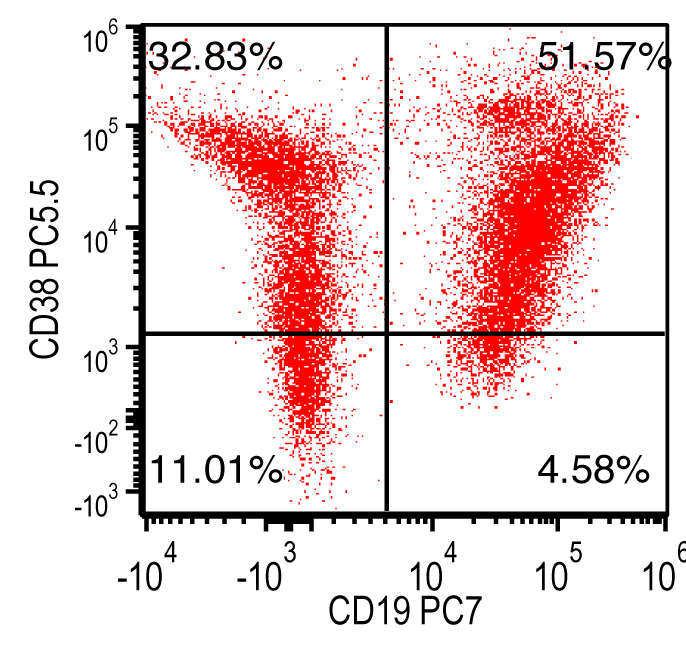

- Flow cytometry: monoclonal B cells with typical immunophenotype and monoclonal plasma cells

- Immunophenotype of LPL cells: IgM+, CD19+, CD20+, CD22+, CD25+, CD10-, CD23-, CD103-, variable CD138

- Immunophenotype

- Positive: IgM, CD19, CD20, CD22, CD79a, CD25 and CD38 frequent expression

- Negative: CD5, CD10, CD103, CD23; however, CD23 expression is not uncommon in some cases

Flow cytometry description

Flow cytometry images

Contributed by Ling Zhang, M.D. and Caroline An, M.D.